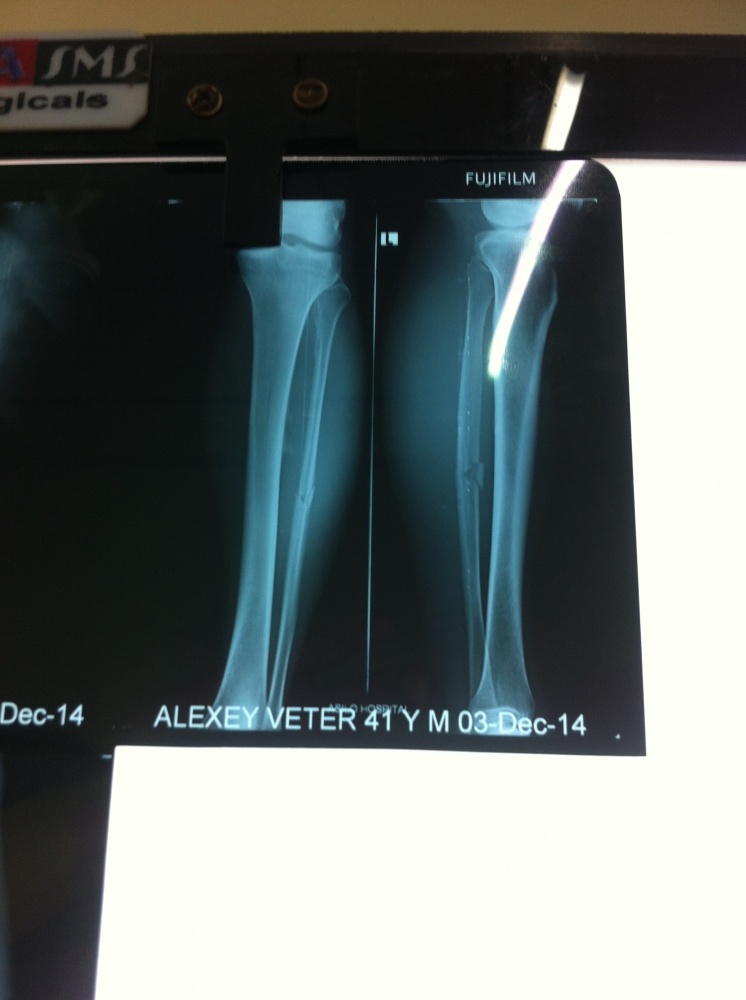

Я приехал к нему домой. На пороге дома какой-то человек предъявил мне удостоверение с надписью «полиция индии» и попросил мои документы. Я сказал, что мой паспорт находится у меня дома и предложил ему проехать со мной, на что мужчина без каких либо слов ударил меня по лицу. Я оттолкнул его от себя, но тут же из дома выбежали еще двое и стали меня хватать. Человек, который меня ударил схватил бревно, которое лежало возле забора. Я побежал. Он стал преследовать меня. На мосту он ударил меня бревном по ноге, после чего я уже не мог бежать. Почти сразу к нему присоединились еще трое и стали избивать меня. Как выяснилось позже, имя одного из мужчин Suraj Holamkap (P-I). Они били меня руками и ногами, били бревном по голове, по рукам, по спине, по ногам. Я понял, что не справлюсь с четырьмя мужчинами и стал кричать «Сдаюсь! Сдаюсь!» однако они не обращали внимания на мои крики и продолжали избивать меня снова и снова, снова и снова. Когда я падал на асфальт, один из них наступал на мою ногу своей ногой, чтобы я не мог двигаться, и они продолжали избивать меня. В какой-то миг я свалился в канаву, заросшую густым кустарником. Это спасло меня. Полицейские не захотели лезть за мной в канаву в кусты и потеряли ко мне интерес. Там я пролежал примерно полчаса. Через полчаса я стал пробираться сквозь кусты и высокую траву позади дома, который находился через дорогу напротив дома Евгения. Я был избит. Мой локоть опух. На голове была огромная шишка с рассечением. Ноги едва двигались. Наступая на левую ногу, я испытывал страшную боль. На следующий день в госпитале города Мапуса мне сделали рентгеновский снимок, который показал, что лучевидная кость моей левой ноги сломана. Сейчас я сижу дома, моя левая нога в гипсе. Мой визит в прекрасную страну Индию превратился в кошмар.